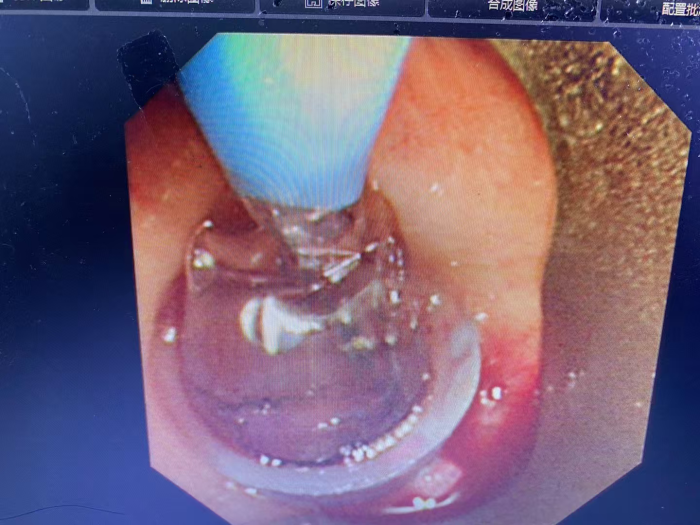

面对紧急情况,呼吸与危重症医学科二病区主任屈东明博士迅速组织麻醉科和内镜中心小组协助急会诊,带领呼吸介入团队李海斌副主任医师一起制定详细手术计划,决定采用全麻下支气管硬镜下肿瘤切除术,在支气管硬镜直视引导下,鞘管成功铲切下一大小约20X15mm肿物,术后患者呼吸困难明显缓解!梁先生终于又可以自由呼吸!